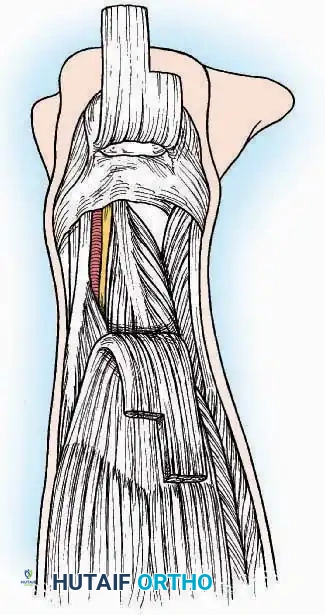

Anterolateral Approach

The anterolateral approach is widely considered the "universal incision" for the foot and ankle. It provides unparalleled access to the ankle joint, the talus, and the majority of the tarsal articulations, while safely avoiding the major anterior neurovascular bundle. The only tarsal joints inaccessible via this route are the naviculocuneiform joints (specifically the medial and intermediate).

Indications: Total talectomy, triple arthrodesis, ankle arthrodesis, and open reduction of complex talar neck fractures.

Surgical Technique:

* Incision: Begin over the anterolateral aspect of the leg, medial to the fibula and 5 cm proximal to the ankle joint line. Carry it distally over the joint, crossing the anterolateral aspect of the talar body and the calcaneocuboid joint, terminating at the base of the fourth metatarsal.

* Superficial Dissection: Incise the superficial fascia and the superior and inferior extensor retinacula down to the periosteum of the tibia and the ankle joint capsule.

* Vascular Ligation: This trajectory usually requires the identification and ligation of the anterolateral malleolar and lateral tarsal arteries.

* Nerve Protection: Retract the skin edges carefully. Identify and protect the intermediate dorsal cutaneous branches of the superficial peroneal nerve (SPN), which frequently cross the distal aspect of this incision.

* Muscle Management: Identify the origin of the extensor digitorum brevis (EDB) muscle on the lateral calcaneus. Divide it in the direction of its fibers, or detach its origin entirely and reflect it distally to expose the subtalar and calcaneocuboid joints.

* Deep Exposure: Retract the extensor digitorum longus (EDL) tendons, the dorsalis pedis artery, and the deep peroneal nerve (DPN) medially. Incise the anterior ankle capsule to expose the tibiotalar joint.

* Tarsal Exposure: Expose the talonavicular joint by dissecting deep to the extensor tendons and incising its capsule transversely. Continue laterally through the capsule of the calcaneocuboid joint. By excising the fat pad within the sinus tarsi (lateral and inferior to the talar neck), the posterior facet of the subtalar joint is brought into direct view.